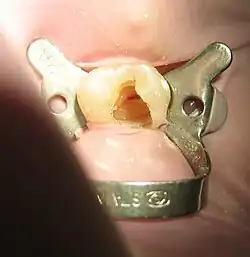

Tooth #13, the upper left second premolar, after excavation of DO decay. There was a carious exposure into the pulp chamber (red oval), and the photo was taken after endodontic access was initiated and the roof of the chamber was removed.